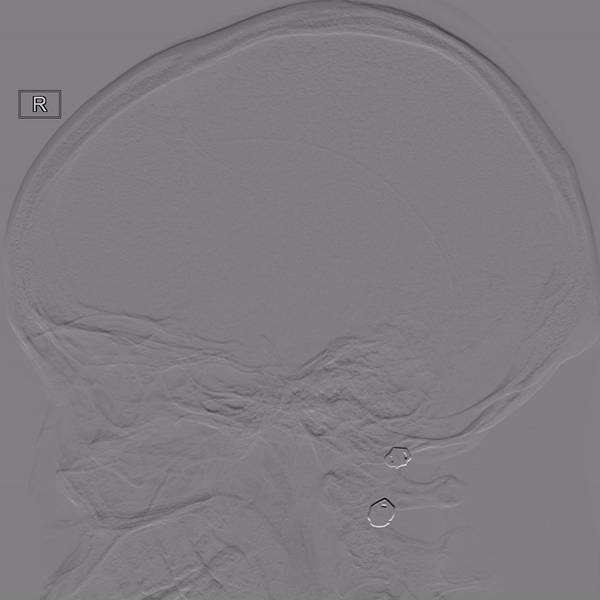

右侧颈内动脉造影

左侧颈内动脉造影